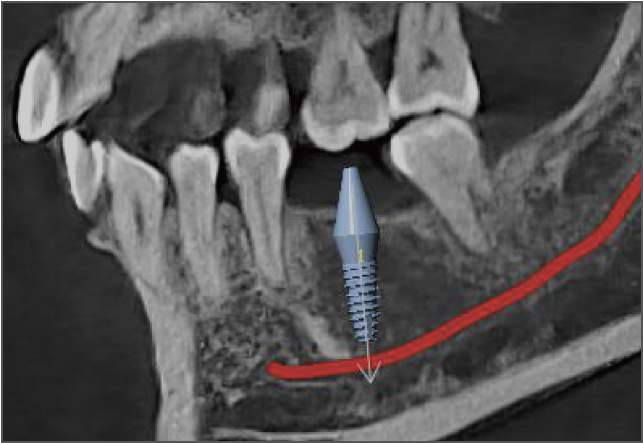

• lamtau 模拟种植

模拟种植

• lamtau AI神经管标记

AI神经管标记